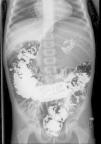

We present 2 cases of chronic gastric volvulus. The first one corresponds to a 5-year-old boy with no underlying disease that came to the emergency department for a second opinion on episodes of intermittent abdominal distension over the course of 1 month. The physical examination was normal except for a mildly distended abdomen with tympanic bowel sounds. A barium transit study was performed on an outpatient basis, the results of which were normal. A few hours later the patient had an episode of abdominal distension and the abdominal radiograph revealed features compatible with gastric volvulus (Fig. 1). Based on these findings, a nasogastric tube was inserted and a laparoscopic surgery performed, revealing a loose gastrocolic ligament that allowed a complete organoaxial gastric volvulus. A phrenofundopexy (fixation of the stomach to the diaphragm) and an anterior gastropexy (fixation of the stomach to the anterior abdominal wall) were performed. The patient had a favourable outcome.

The diagnosis is usually made by an abdominal radiograph and an upper gastrointestinal series,3 although the results of these studies may be normal.4 Thus, other imaging techniques, such as CAT, may be required if there is a high clinical suspicion and the previously mentioned studies are all normal. Depending on the axis of rotation, the volvulus is classified as organoaxial (54% of acute cases and 85% of chronic cases),1 mesenteroaxial (41% of acute and 10% of chronic cases),1 or combined.5 The findings may include gross gastric distension, abnormal position of the stomach, and two air-fluid levels in imaging studies with a “bird's beak appearance” at the esophagogastric junction, among others. In organoaxial volvulus, the stomach lies on a horizontal plane with the greater curvature superior to the lesser curvature. In mesenteroaxial volvulus, the gastroduodenal junction is superior to the oesophagogastric junction, and the stomach plane is vertical and has a spherical appearance.